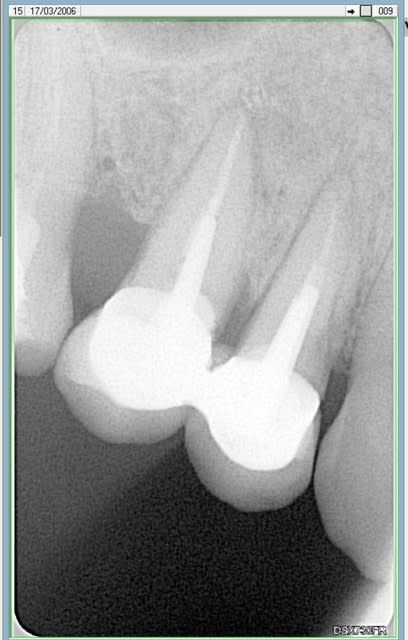

regarde sur la molaire , j'ai différé l empreinte de 7 jours.

la photo est le jour de l'empreinte , or le jour de la taille j'etais juxta voire infra .

si j'avais pris l'empreinte le meme jour je l'aurais eu gros...